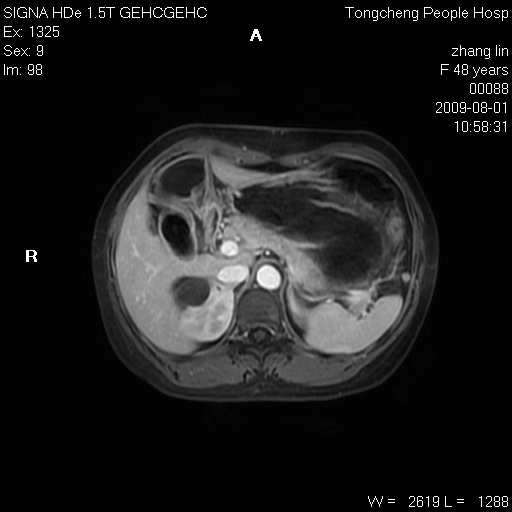

女,48岁。健康体检,彩超发现右肾占位性病变。平素健康。

临床诊断:右肾占位性病变,性质待定(囊肿?肿瘤?)。

上中腹部mr平扫+增强扫描,图像如下:

右肾上极见一类圆形病灶,t1wi呈等信号t2wi呈等高混杂信号,三期增强无强化,边界清---考虑囊肿出血。

同反相位均表现为等信号,病变无强化,考虑含蛋白的囊肿可能,弥散加权相或许有些帮助,